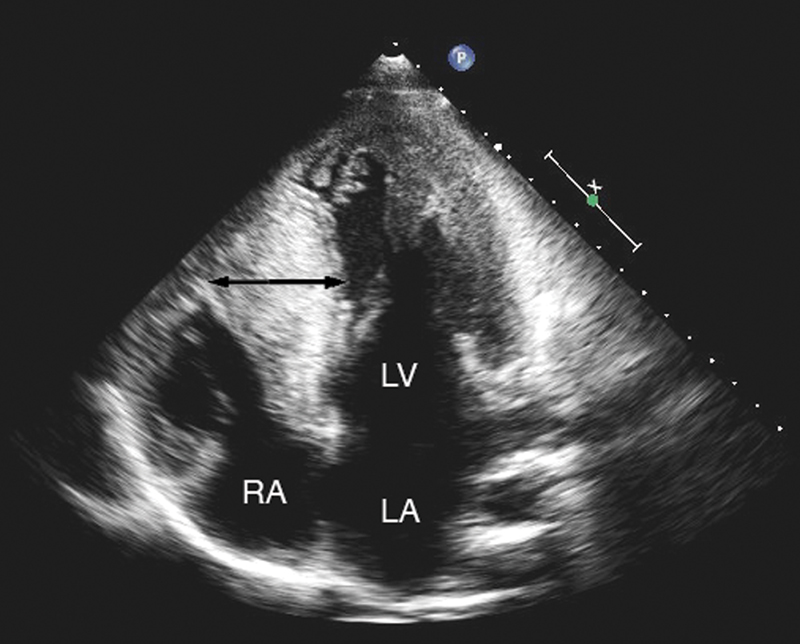

فحوصات تشخيصية لبعض امراض القلب والشرايين التاجية